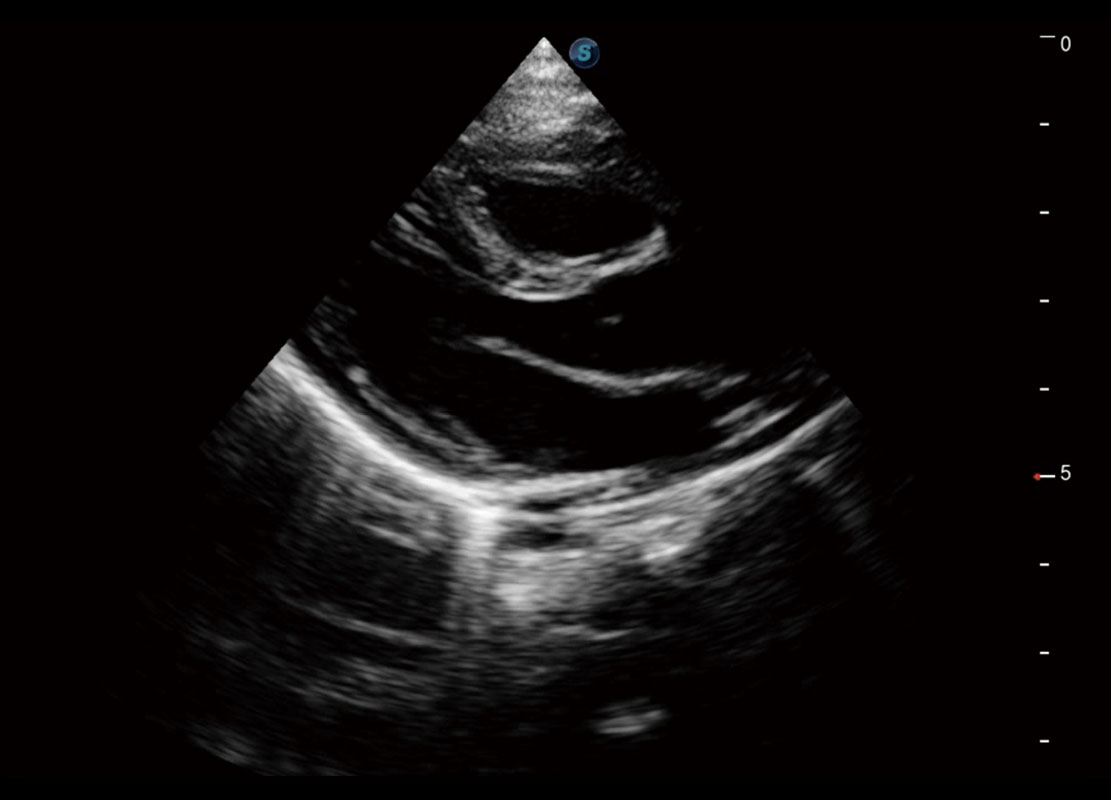

• 四腔切面

• 四腔心血流

P60搭载一系列胎儿心脏成像技术,实现精细的胎儿心脏评估。